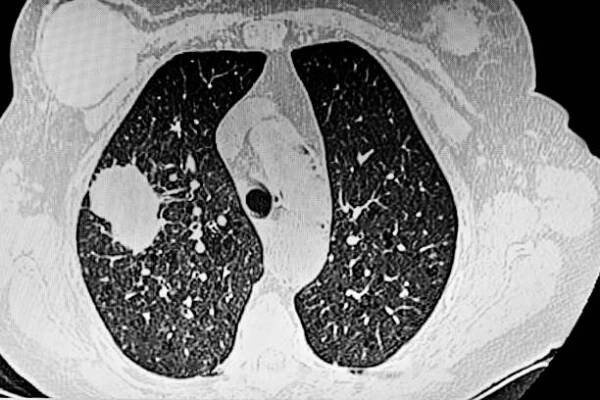

cat sken plic ukazující nádor adenokarcinomu - ct scan lung - stock snímky, obrázky a fotky

cat scan obrázek plicní angiografie ukazující adenokarcinom plic - ct scan lung - stock snímky, obrázky a fotky